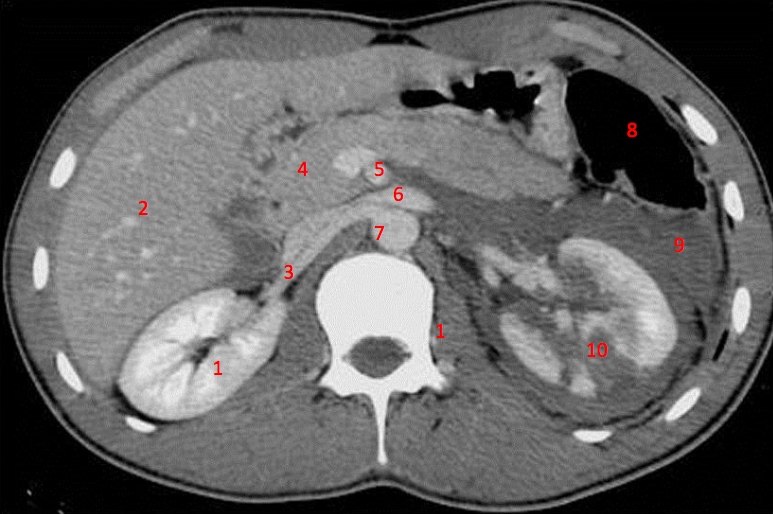

Number 1?

R Kidney

Number 4?

Rectus abdominus

Head of pancreas

Rt diaghragmatic crus

Number 5?

Rt ureter

Number 9?

Superior mesenteric artery